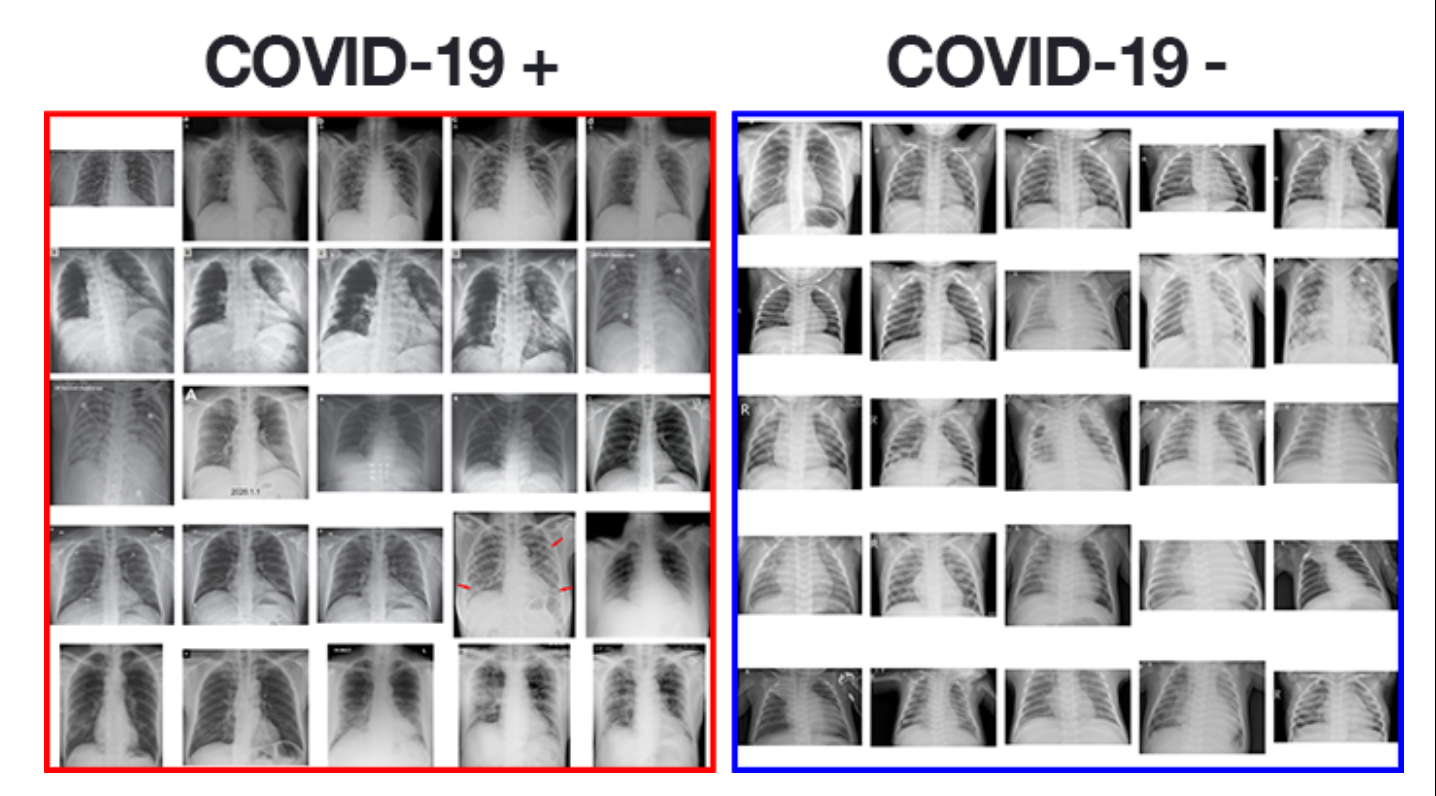

Поражение легких является одним из основных симптомов коронавируса (COVID-19). В данной статье представлены фото рентгеновских снимков, которые позволяют визуально оценить состояние легких при этом заболевании.

На фотографиях рентгеновских снимков видно, как вирус воздействует на легочную ткань. Характерные признаки поражения легких включают пятна, инфильтраты и наличие жидкости внутри легочных альвеол.

Фото рентгеновских снимков помогают врачам и специалистам визуально определить степень поражения легких и принять соответствующие меры лечения и поддержки пациента.